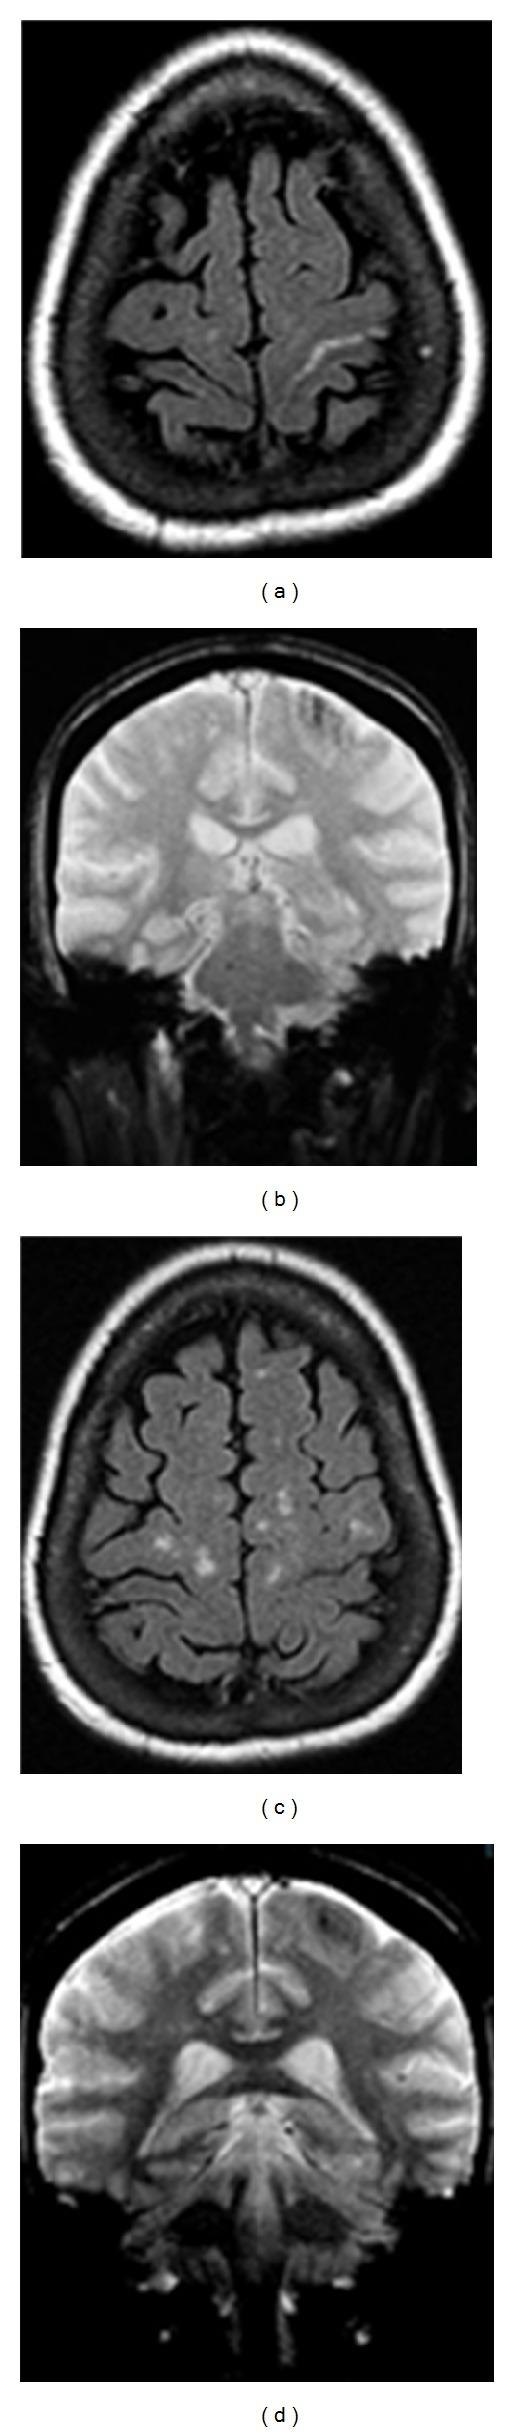

Central sulcus hemorrhage is a rare imaging finding that can be related to cerebral amyloidosis in a normotensive non-traumatic elderly patient and present as an isolated finding or in association with other areas of involvement. We report a case presenting with an isolated central sulcus hemorrhage on computed tomography. Further imaging work-up excluded other potential causes of peripheral hemorrhages and established a putative diagnosis of cerebral amyloidosis.

中央沟出血是一种罕见的影像学表现,在血压正常、非创伤性的老年患者中可能与脑淀粉样血管病相关,可表现为孤立性发现或伴有其他受累区域。我们报告一例计算机断层扫描显示孤立性中央沟出血的病例。进一步的影像学检查排除了外周出血的其他潜在原因,并初步诊断为脑淀粉样血管病。